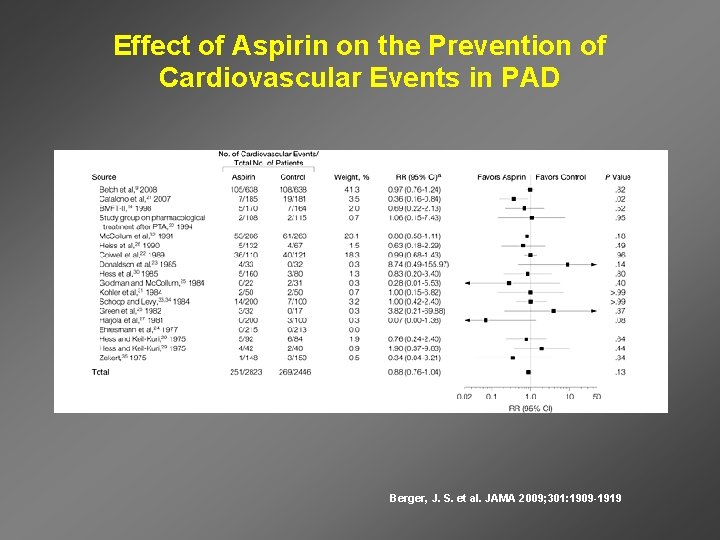

Effect of Aspirin on the Prevention of Cardiovascular Events in PAD Berger, J. S. et al. JAMA 2009; 301: 1909 -1919